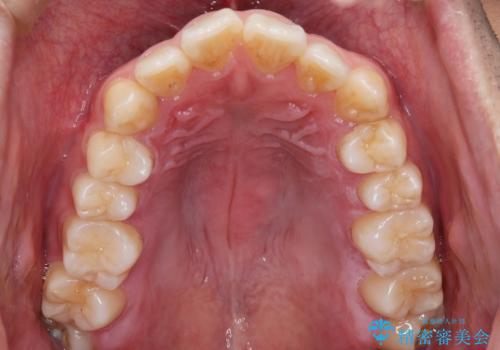

- 上の歯が出ているのが気になるのを主訴にご来院されました。人前で話すお仕事をされており目立たないマウスピース治療を希望されていました。

口元のEラインは気にならないとのことだったのでインビザラインにて治療していくことにしました。

IPR(歯と歯の間を削る処置)と歯列拡大をすることで前歯を少し下げ、がたつきを改善していく治療計画を立てました。

上の前歯が出ているという主訴が綺麗に改善されました。

その他の部位のがたつき、奥歯の噛み合わせも以前と比べると良くなっています。